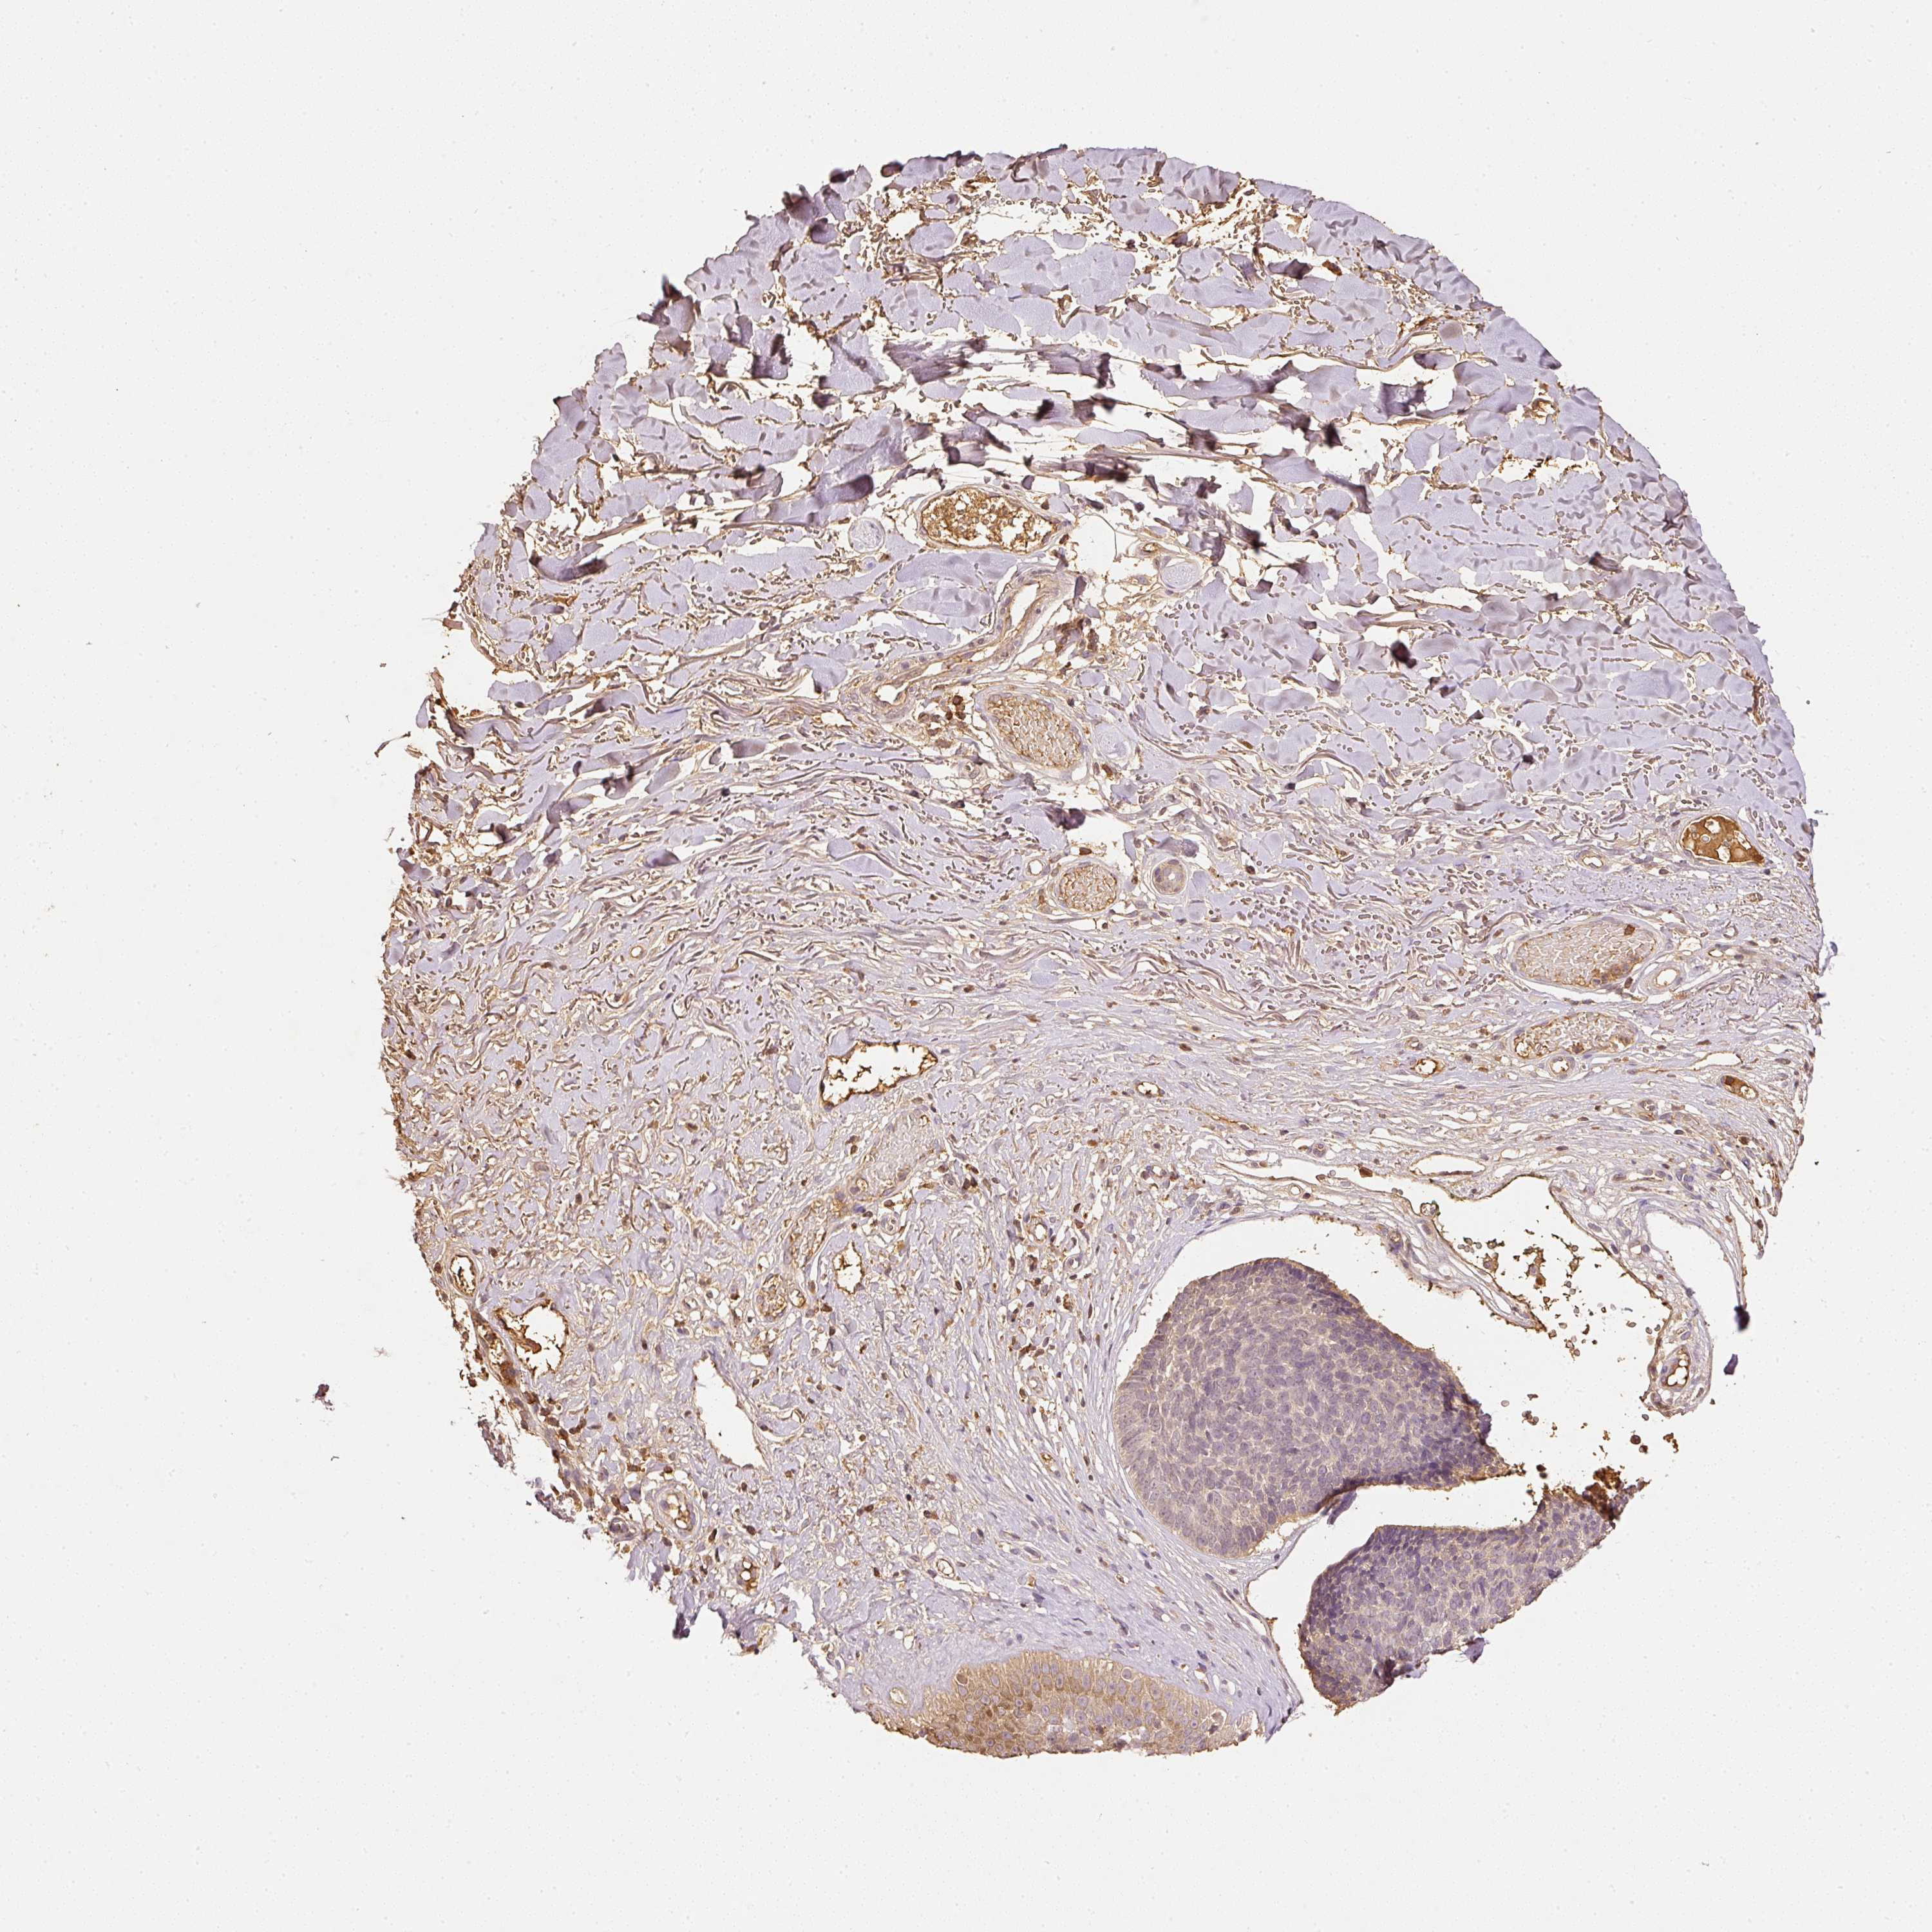

SKIN CANCER - Protein expressioni

A mouse-over function shows sample information and annotation data. Click on an image to view it in a full screen mode. Samples can be filtered based on level of antibody staining by selecting one or several of the following categories: high, medium, low and not detected. The assay and annotation is described here.

Each image is clickable and will lead to virtual microscopy that enables deeper exploration of all samples and also displays staining intensity scores, fraction scores and subcellular localization as well as patient and tissue information for each sample.

Antibody HPA018849

Basal cell carcinoma